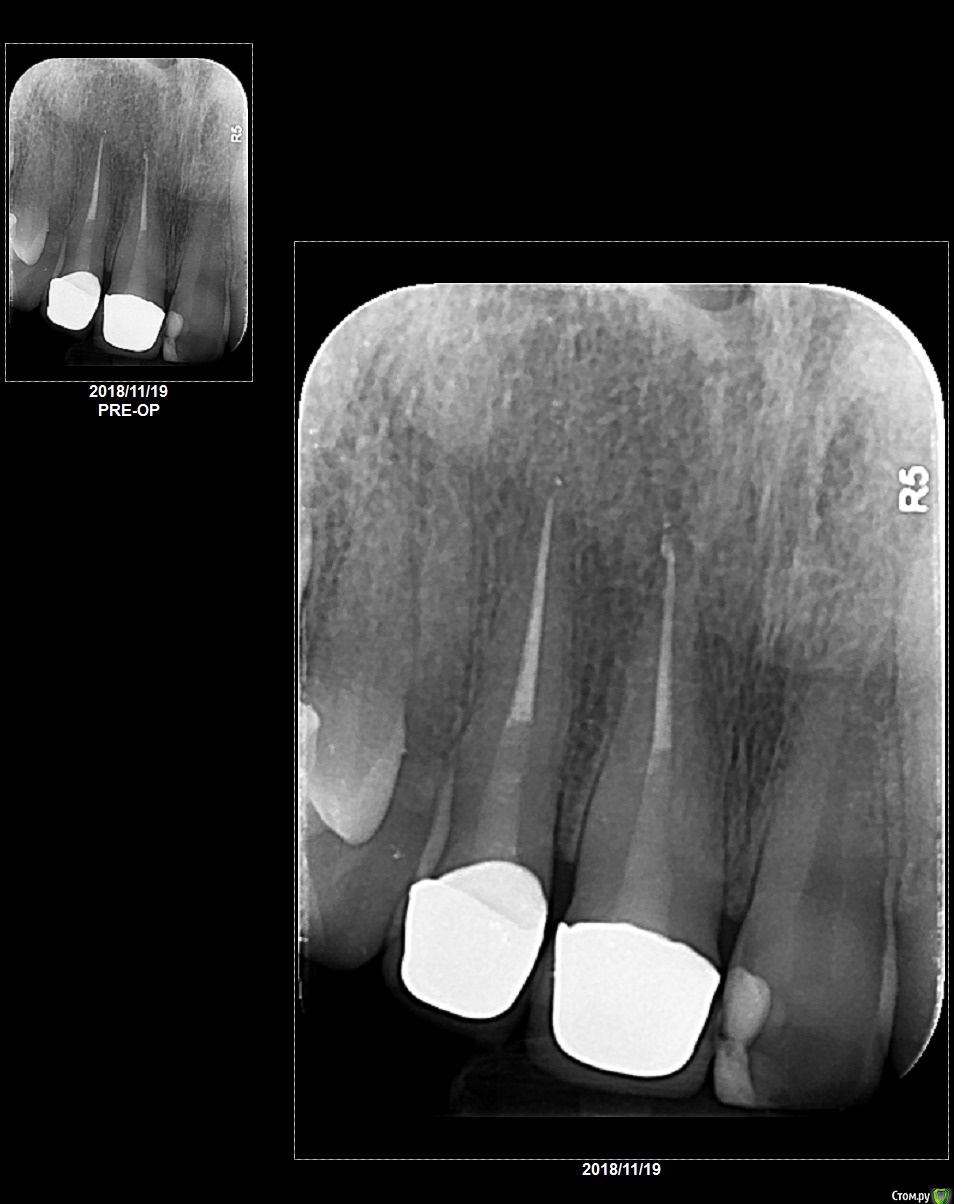

9 октября мне на два передних зуба (без нервов 12 лет) установили коронки емакс, под них - цельнокерамические вкладки (цирконий). Причина установки - эстетическая, зубы потемнели, пломбы выделялись, сами зубы не беспокоили.

16 ноября центральный резец под коронкой начал беспокоить (я начала его чувствовать, как будто он мне мешает - ощущение нельзя назвать болью, скорее, чувство тяжести с чем-то вроде распирания). Зуб под второй коронкой такой реакции не давал вообще. Но также начали беспокоить десны над обеими коронками - они немного посинели и воспалились, ныли, но не было ни запаха, ни крови. Зубы не шатаются. Проблема в том, что вкладки и коронки мне ставили в родном городе в России, а постоянно проживаю я на другом континенте (куда вернулась 3 ноября). Так что с врачом, который мне делал вкладки о коронки, я смогла связать только по интернету, предоставив свежий снимок. Он меня заверил, что все в порядке, каналы на снимке идеальны (их перепломбировали под коронки), снимок хорошего качества, просто чем-то натерла десну. Я совершенно точно не ела ничего жесткого ( в октябре мне удалили два жевательных зуба, так что я до сих пор ничего твердого есть не решаюсь). По совету врача, я мазала десну солкосерилом и метрогилом, но спустя неделю ситуация не улучшилась, и я побежала к местному специалисту (страна, в которой я сейчас живу, не первый мир, именно этим был обусловлен выбор российского специалиста из рекомендованной многими клиники).

Местный врач по снимку подтвердил, что нет ни воспаления корня, ни проблем с каналами, но его осмотр показал, что зубы препарированы под коронки слишком глубоко и нарушена биологическая ширина. Таким образом, коронки давят, отсюда и страдания. И мол, это вопрос решаемый, но нужно снимать коронки, делать небольшую операцию на деснах. Коронки позавчера сняли, поставили временные, после этого я весь день так же чувствовала центральный резец, соседний зуб из под коронки так же не беспокоил. На второй и третий день неприятные ощущения, присутствовавшие почти 2 недели, прошли. Но легкую тяжесть централнього резца по сравнению с соседним зубом я чувствую (возможно, я себя накручиваю, возможно вес коронки, а возможно и нет). Кусать не пробовала, т.к. коронки временные.

Я прочитала, что цельнокерамические вкладки из диоксида циркония - верный путь к трещине корня, и теперь у меня паранойя. Вдруг мои ощущения обусловлены какой-то трещиной, которую не видно на снимке? И если я сейчас заменю коронки, то через пару месяцев меня ждет то же самом или что-то похуже - воспаление с невозможностью имплантации. Приходят мысли, не проще ли сразу поставить имплант и не мучиться, но поскольку это дело дорогостоящее и долгое, плюс все-таки зуб в зоне улыбки решение принять сложно(. Российский врач утверждает, что вкладки сделаны идеально, но он так же и утверждает, что ничего мне глубоко не препарировал и вообще всё дело в том, что я что-то сильно укусила (это, повторюсь, исключено, врать совершенно не в моих интересах, в моих интересах решить проблему).

Снимок прилагаю.post-56516-0-93511100-1543699303_thumb.jpg

на вашем снимке трещин не видно, возможно более информативно было бы КТ, но ваши предположения верны,  я бы тоже рекомендовал не переживать раньше времени и  походить с временными коронками.